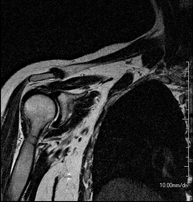

- RM d'Espatlla

Exploració per a l'estudi de lesions en els tendons, els músculs i les articulacions. La seva principal utilitat resideix en diagnosticar les lesions dels tendons del braçal rotatori. Té una durada aproximada de 20 minuts. No utilitza radiació ionitzant. - RM de Braç